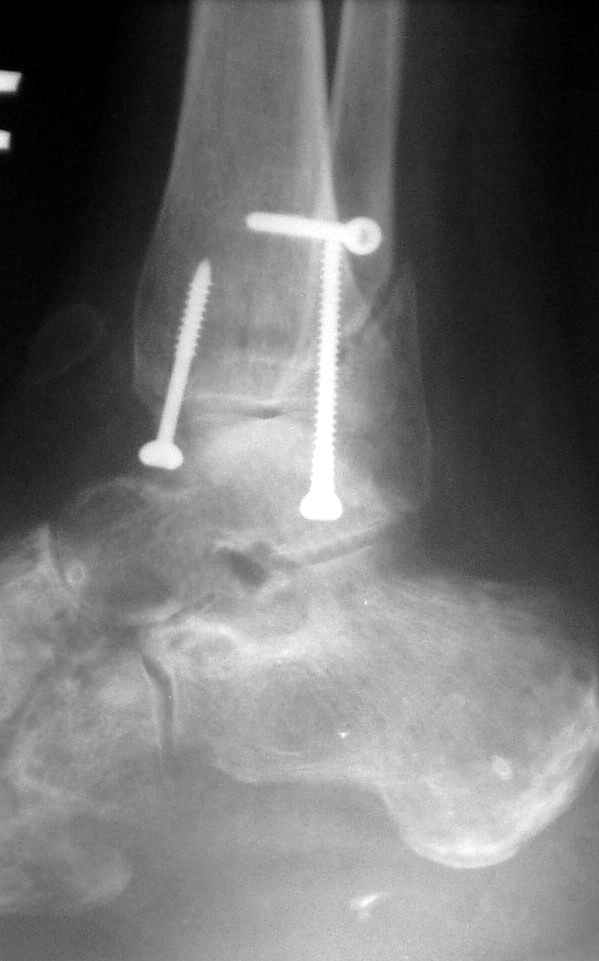

15 ноября боковой

15 ноября трехчетвертной